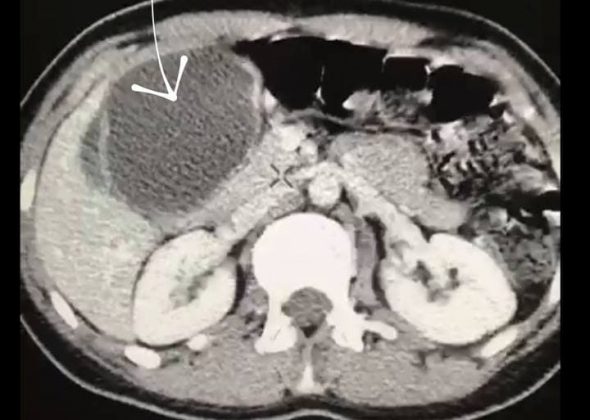

В Раменскую больницу поступила женщина с жалобами на резкие боли в животе. В результате проведенной диагностики у пациентки выявили эхинококковую кисту размером 8х12 см, занимающую всю левую долю печени.

«Хирургами была выполнена сложнейшая операция по удалению эхинококковой кисты, при этом удалось сохранить всю левую долю печени. В ходе удаления новообразования, крайне важно не повредить оболочку кисты, тем самым, не дать выход ее содержимому, которое за считаные минуты обсеменяет орган, вызывая мощнейшую интоксикацию, ведущую к смерти в течение 1-2х часов. Тем не менее, и жить с эхинококкозом крайне опасно. Киста непрерывно растет в размерах, сдавливая ближайшие сосуды и препятствуя нормальному кровотоку в органе», — рассказал кандидат медицинских наук, заместитель главного врача Раменской больницы по хирургической помощи Дмитрий Зинатулин.